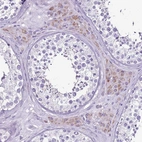

Immunohistochemical staining of human kidney shows strong cytoplasmic positivity in cells in tubules.